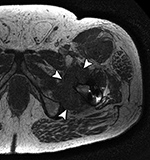

Adverse reaction to metal debris with anterior pseudotumor. Axial T1-weighted MR image shows large soft tissue mass (arrowheads) centered at the level of the lesser trochanter with involvement of the iliopsoas attachment site in a patient with metal-on-metal hip arthroplasty. Also note infiltrative involvement of the rectus femoris muscle.

On MRI, pseudotumors will appear as solid, cystic or mixed masses adjacent to and possibly communicating with the hip joint with potential intralesional or peripheral low T2 signal, reflecting metal deposition (Figure 24) (Chen, 2011). Solid lesions more commonly occur anteriorly, usually within the psoas muscle and may extend proximally into the pelvis (Figure 25) (Ostlere, 2011). Predominantly cystic lesions typically arise from the posterior joint space and may or may not demonstrate wall-thickening. Lateral lesions usually involve the trochanteric bursa and often communicate with the joint space. Differentiation of cystic and solid lesions may be difficult and the use of post-contrast imaging is not helpful for lesion detection, particularly due to surrounding metallic artifact. There may be involvement of the adjacent osseous structures with associated erosions, as well as the soft tissues, particularly the gluteal tendon attachments with resulting tendon disruption and muscle atrophy (Figure 26) (Anderson, 2011). In rare cases, the reactive process may involve pelvic or lower extremity arteries or the femoral nerve, particularly when occurring anteriorly (Clayton, 2008; Chen, 2011). At present, there is no established pathway for the management of metal-on-metal pseudotumor patients, and follow-up imaging may be performed to assess lesion progression before proceeding to revision, especially with small lesions or minor symptoms.